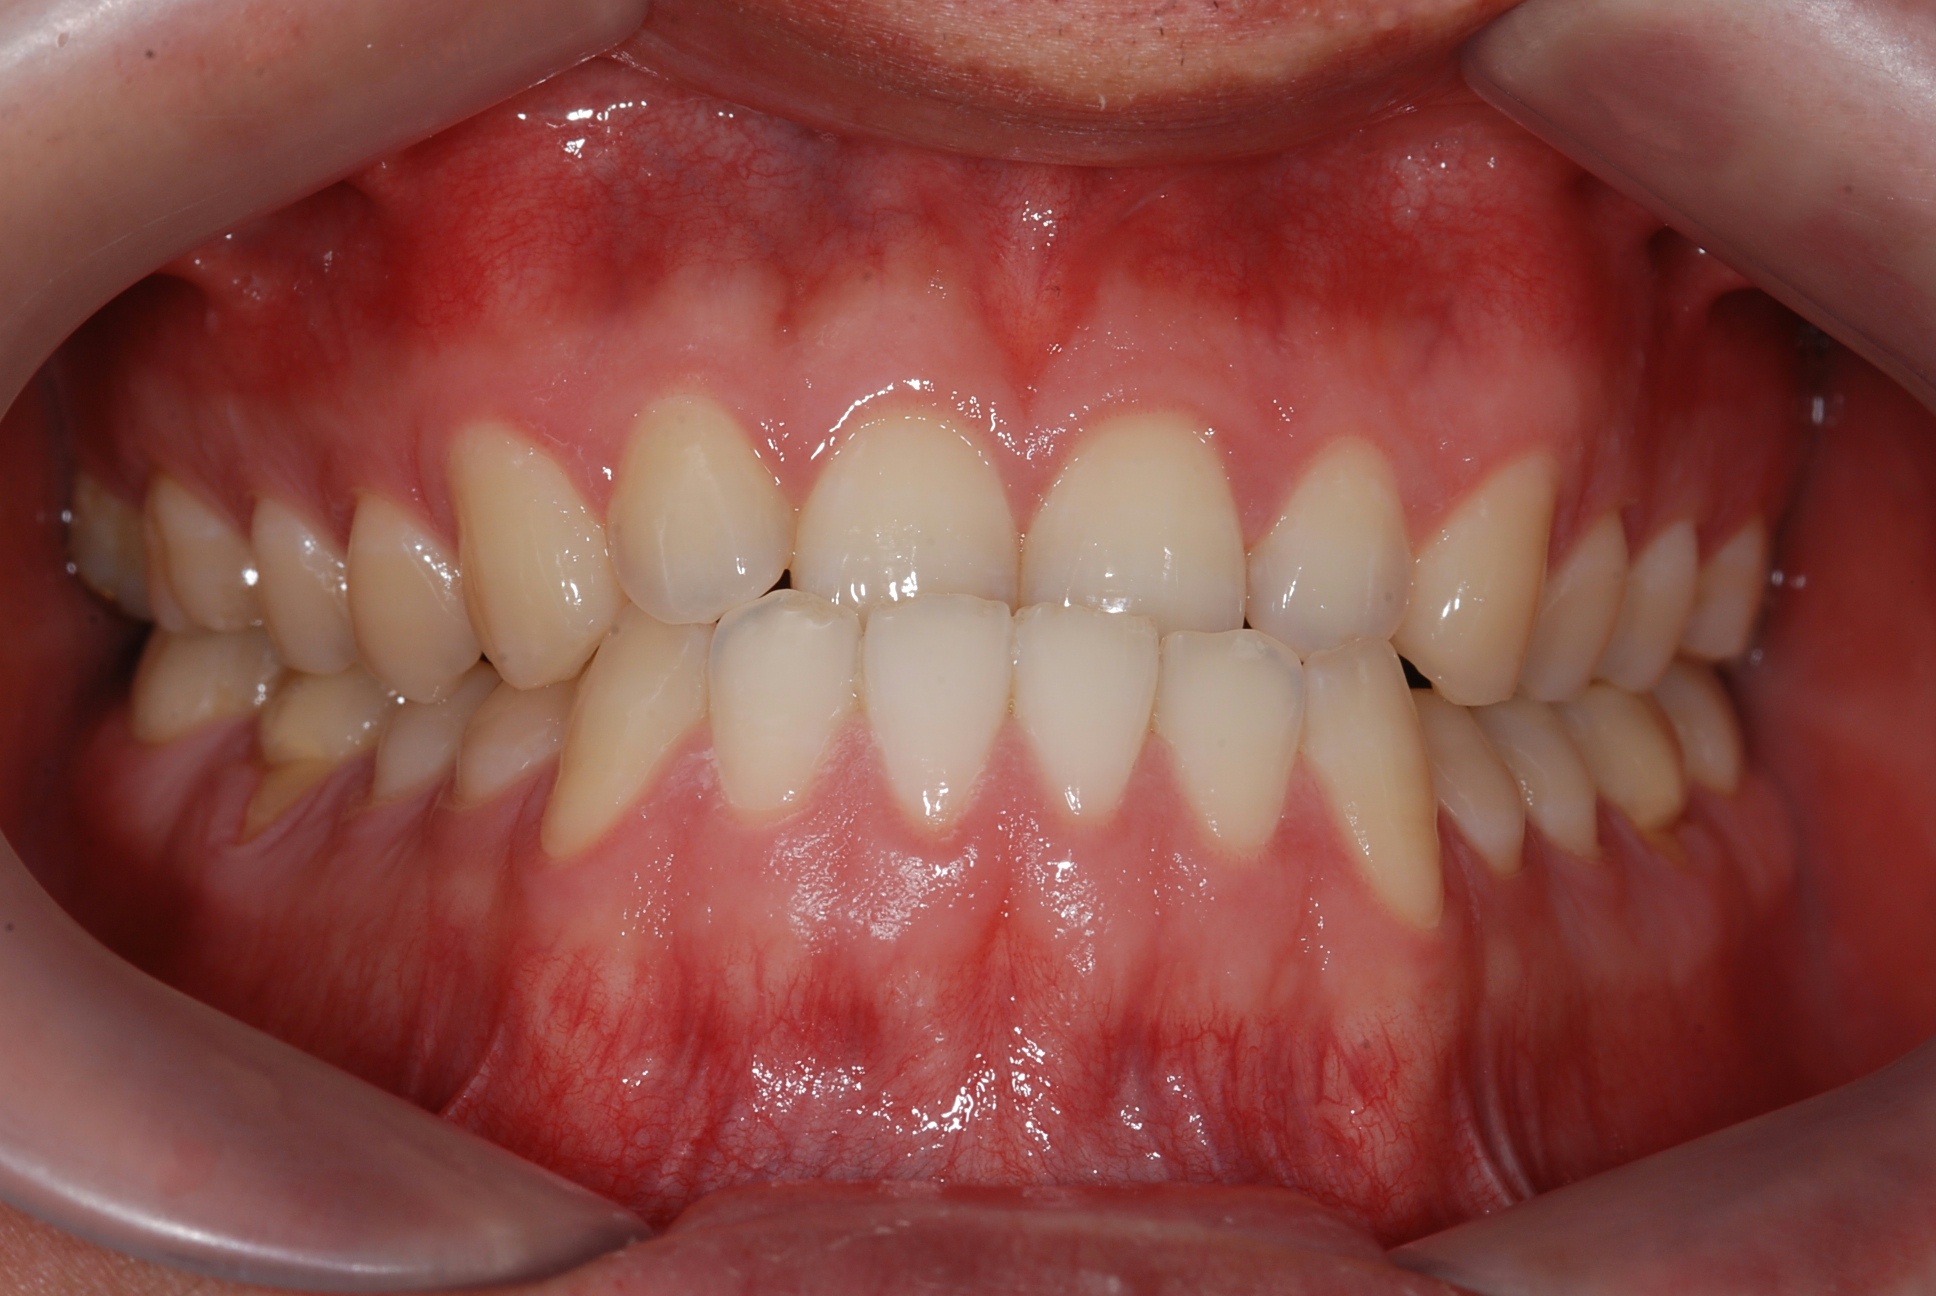

치료 전 사진입니다.